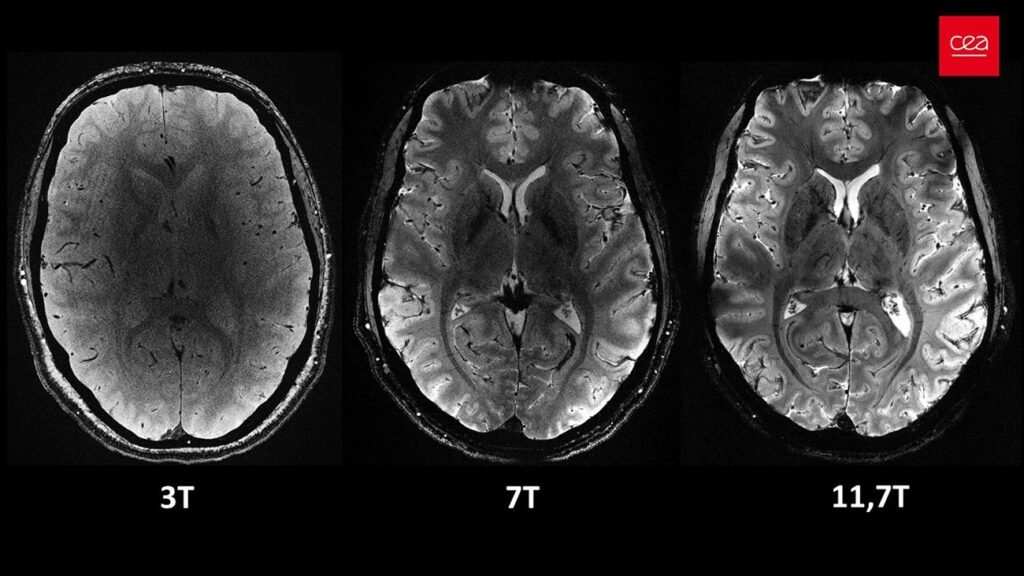

دستگاه Iseult MRI که توسط «کمیسیون انرژی‌های جانشین و انرژی اتمی فرانسه» یا CEA گسترش یافته، دارای قوت میدان مغناطیسی ۱۱.۷ تسلا است. برای قیاس، دستگاه‌های MRI معمولی که امروزه در بیمارستان‌ها مورد منفعت گیری قرار می‌گیرند، طبق معمولً ۱.۵ یا حداکثر ۳ تسلا قوت دارند. Iseult چند سال پیش روی کدو‌تنبل آزمایش شد، اما اکنون در مجموعه‌ای از آزمایش‌ها برای اولین‌بار مغز ۲۰ داوطلب سالم را اسکن کرده است.

مزیت مهم در این دستگاه، قوت بالای آن است که می‌تواند با شدت زیادتری تصاویری با وضوح زیاد بالا از مغز بگیرد. Iseult تنها در چهار دقیقه می‌تواند تصاویری با وضوح ۰.۲ میلی‌متری از بافت مغز را به‌صورت افقی، در برش‌هایی به ضخامت ۱ میلی‌متر ثبت کند. این حجم معادل ثبت چند هزار نورون در یک زمان اشکار است.